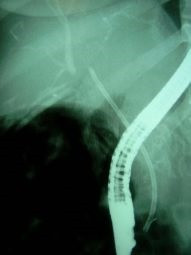

Lesión de conducto hepático derecho post colecistectomía

Envíado por Dr. Carlos Miguel Zavaleta Consuegra